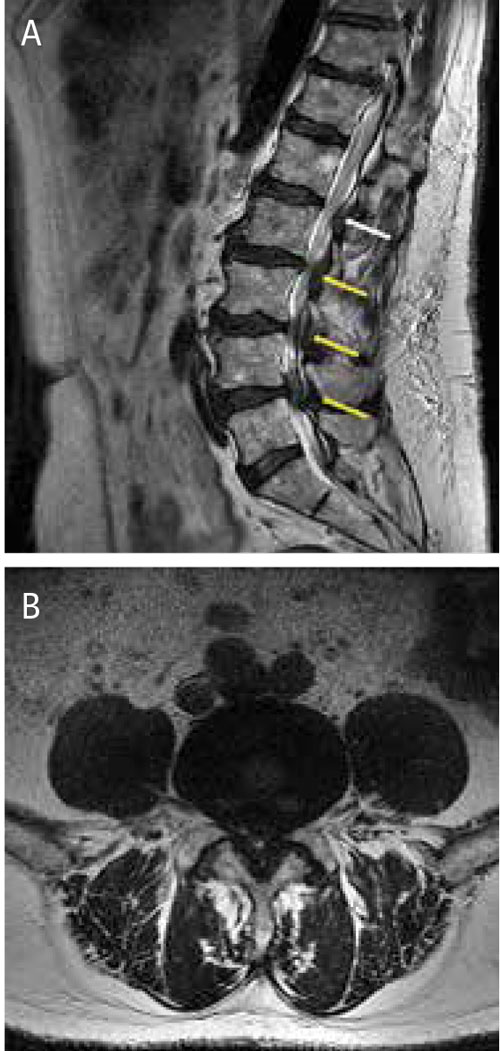

MRT-bilder med T2-­sekvens av lumbalryggen hos patient med central lumbal stenos i flera nivåer: A) Sagittalt medellinjesnitt där tydlig central stenos ses i nivå L 2–L 5 (gula pilar) och möjlig stenos i L 1–L 2 (grå pil). B) Axialsnitt från L 4–L 5-nivå visar kraftig central och lateral stenos orsakad av en kombination av framför allt diskbuktning och förtjockade ligament.